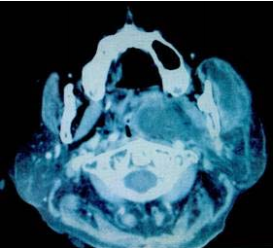

再依據電腦斷層掃描影像如圖 ,可以得知最正確的診斷為何? (A)右側顴骨弓骨折 (B)右側上顎骨骨折 (C)右側顴骨骨折 (D)右側顴骨及顴骨弓骨折

53.承上題,造成病人張口疼痛困難(Trismus)的原因中,最不可能的是那一項? (A)斷骨處疼痛,因而不敢亂動 (B)右側顏面神經受傷 (C)顴骨弓內陷,阻礙下顎喙狀突張口時的正常運動路徑 (D)右側咬肌、顳肌受傷痙攣